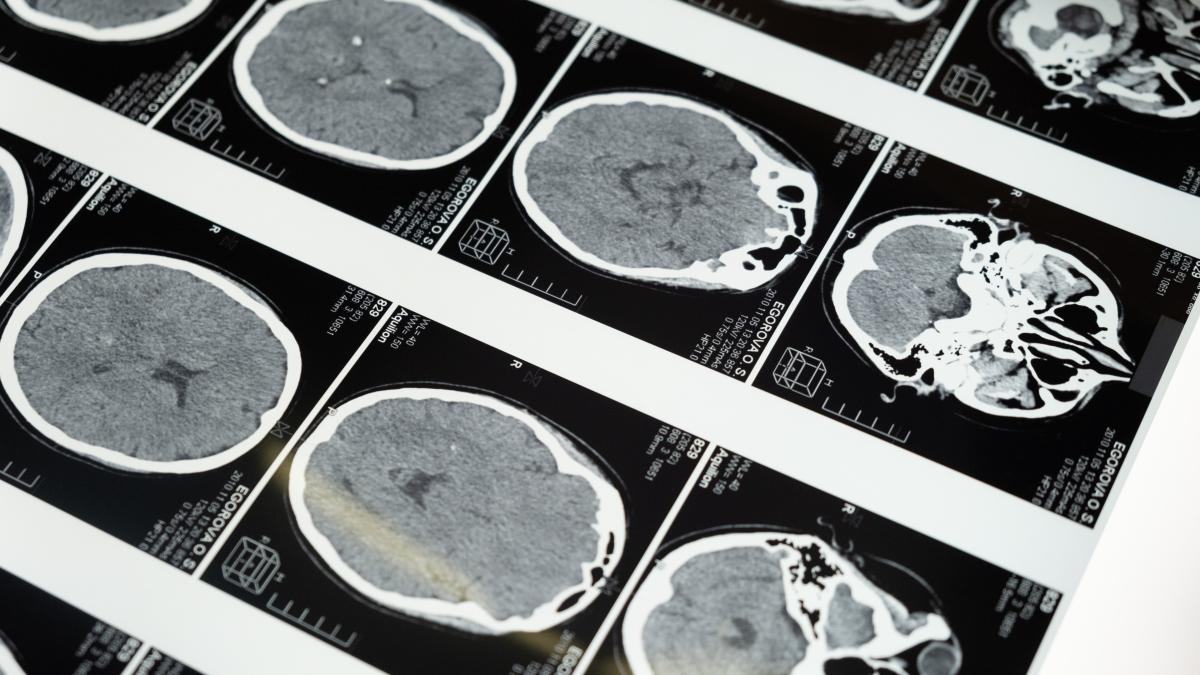

moment-istoric-in-tratarea-alzheimer_01589500 Foto cu caracter ilustrativ: Pexels

În cadrul studiului, care a cuprins aproximativ 1.800 de pacienți cu boala Alzheimer în stadiu incipient, pacienților li s-au administrat perfuzii de două ori pe săptămână cu respectivul medicament, numit lecanemab. S-a demonstrat că medicamentul reduce plăcile toxice, încetinește declinul memoriei și capacitatea pacienților de a îndeplini sarcinile de zi cu zi. În același timp, aproximativ o cincime dintre pacienți au prezentat efecte secundare, inclusiv umflarea creierului sau sângerări cerebrale vizibile la scanările PET. Aproximativ 3% dintre acești pacienți au prezentat efecte secundare simptomatice.